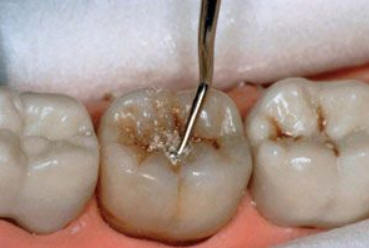

Sólo se lleva a cabo en  cavidades pequeñas ( que involucra solo la dentina ) y en aquéllas que son accesibles para los instrumentos de mano. Con el instrumental de mano se elimina la dentina desorganizada e infectada hasta llegar a la dentina desmineralizada. Ver figura inferior.

Instrumental necesario para el TRA: Pinza para algodón, espejo bucal y explorador como instrumental de exploración y preparación del campo.

Cucharitas de Black o pequeños excavadores para eliminar tejido cariado. Hachuela y azadón para el tallado del ionómero vítreo.

Se aísla el campo operatorio con rollos de algodón. Se limpia la cavidad con una torunda de algodón embebida en agua y luego se seca con torunda. Se utiliza la hachuela para ampliar la cavidad de caries, luego se elimina la caries con  cucharitas o excavadores.

Preparar el ionómero vítreo como indican la instrucciones del fabricante. Obturar con ionómero la cavidad y las fisuras remanentes.

Frote el  índice enguantado con vaselina y el material del relleno se aprieta firmemente con el dedo en el diente. Espere unos minutos y comience el tallado del material con el azadón.

La obturación terminada debe abarcar todas las fosas y fisuras,.